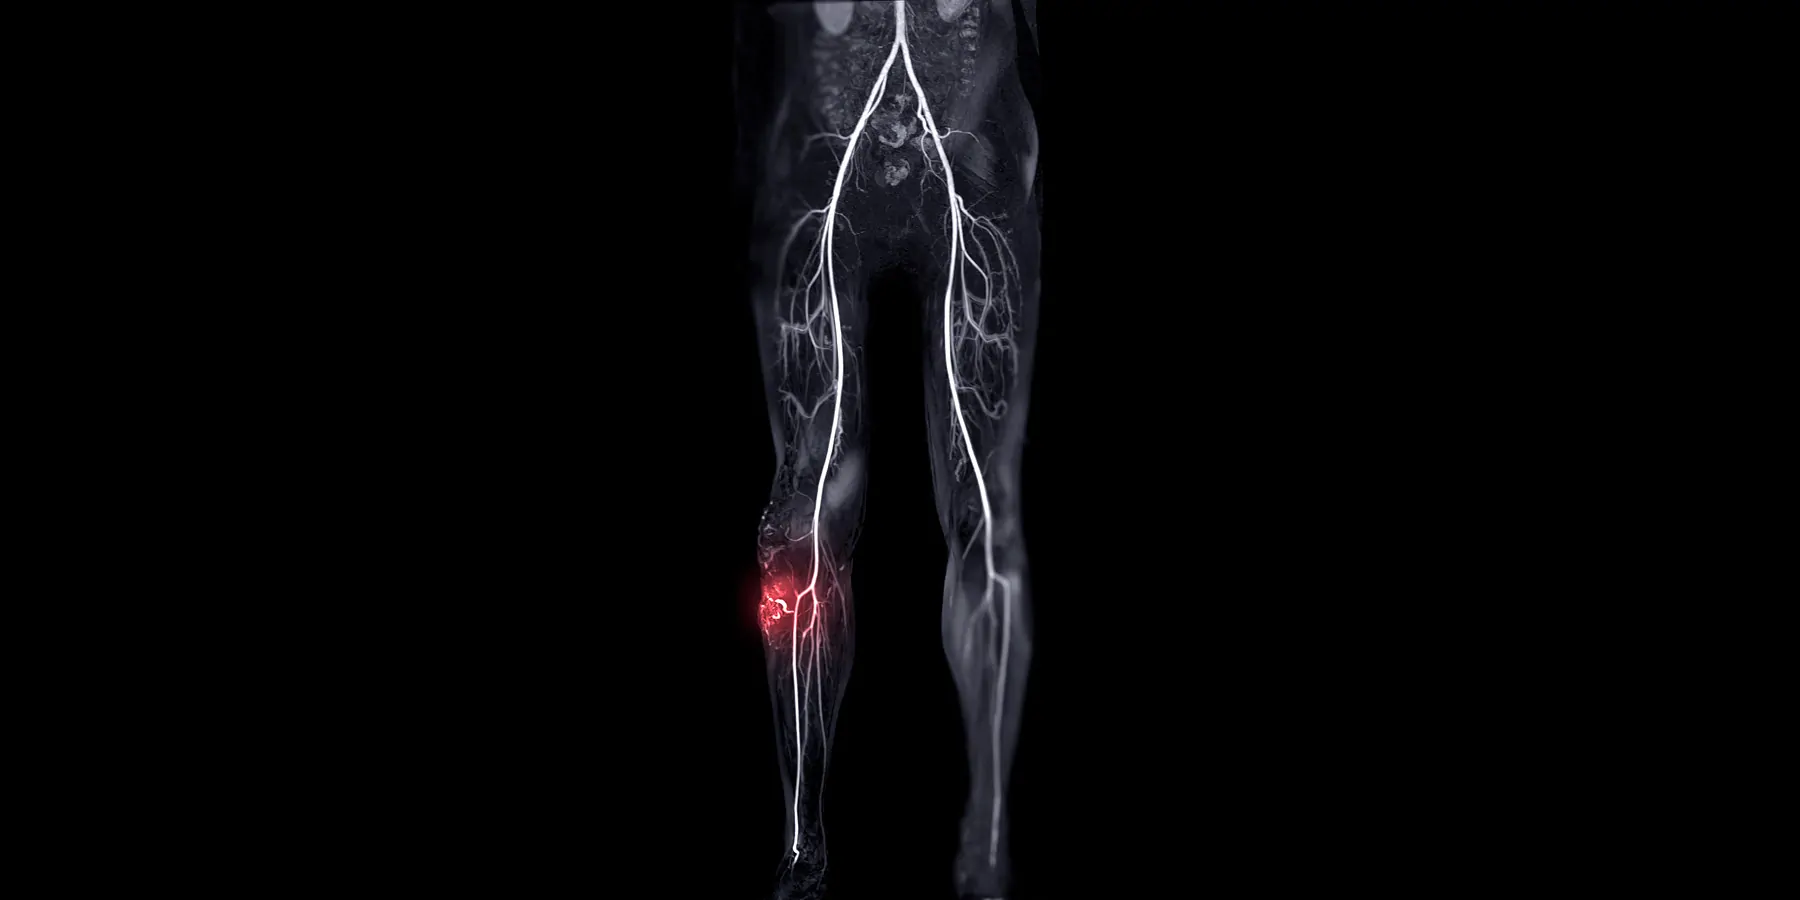

More than 200 million people worldwide have peripheral artery disease (PAD) and more than 1-in-10 have a severe form of PAD known as chronic limb threatening ischemia (CLTI), putting them at risk of leg amputation, cardiovascular disease, and death. Two forms of treatment—surgical bypass (Bypass) and endovascular therapy (Endo)—are commonly used to restore blood flow to the leg, but it has been largely unknown which treatment approach leads to better outcomes for patients. A randomized, multicenter, international clinical trial led by investigators from Mass General Brigham’s founding members, Brigham and Women’s Hospital (BWH) and Massachusetts General Hospital (MGH), and Boston Medical Center (BMC), compared important clinical, patient experience and cost outcomes for the two approaches. The results of the BEST-CLI trial were simultaneously published in the New England Journal of Medicine and presented at the American Heart Association Scientific Sessions.

Both Bypass and Endo are considered standard-of-care treatment for patients with CLTI. For patients who receive Endo, a blockage in their artery is opened with a balloon and a wire mesh stent may be inserted permanently to maintain the opening. This procedure has become increasingly common in recent years. For Bypass, surgeons create a detour or "bypass" around the blockage in the patient’s artery by inserting a vein or a synthetic tube when an adequate vein is unavailable.